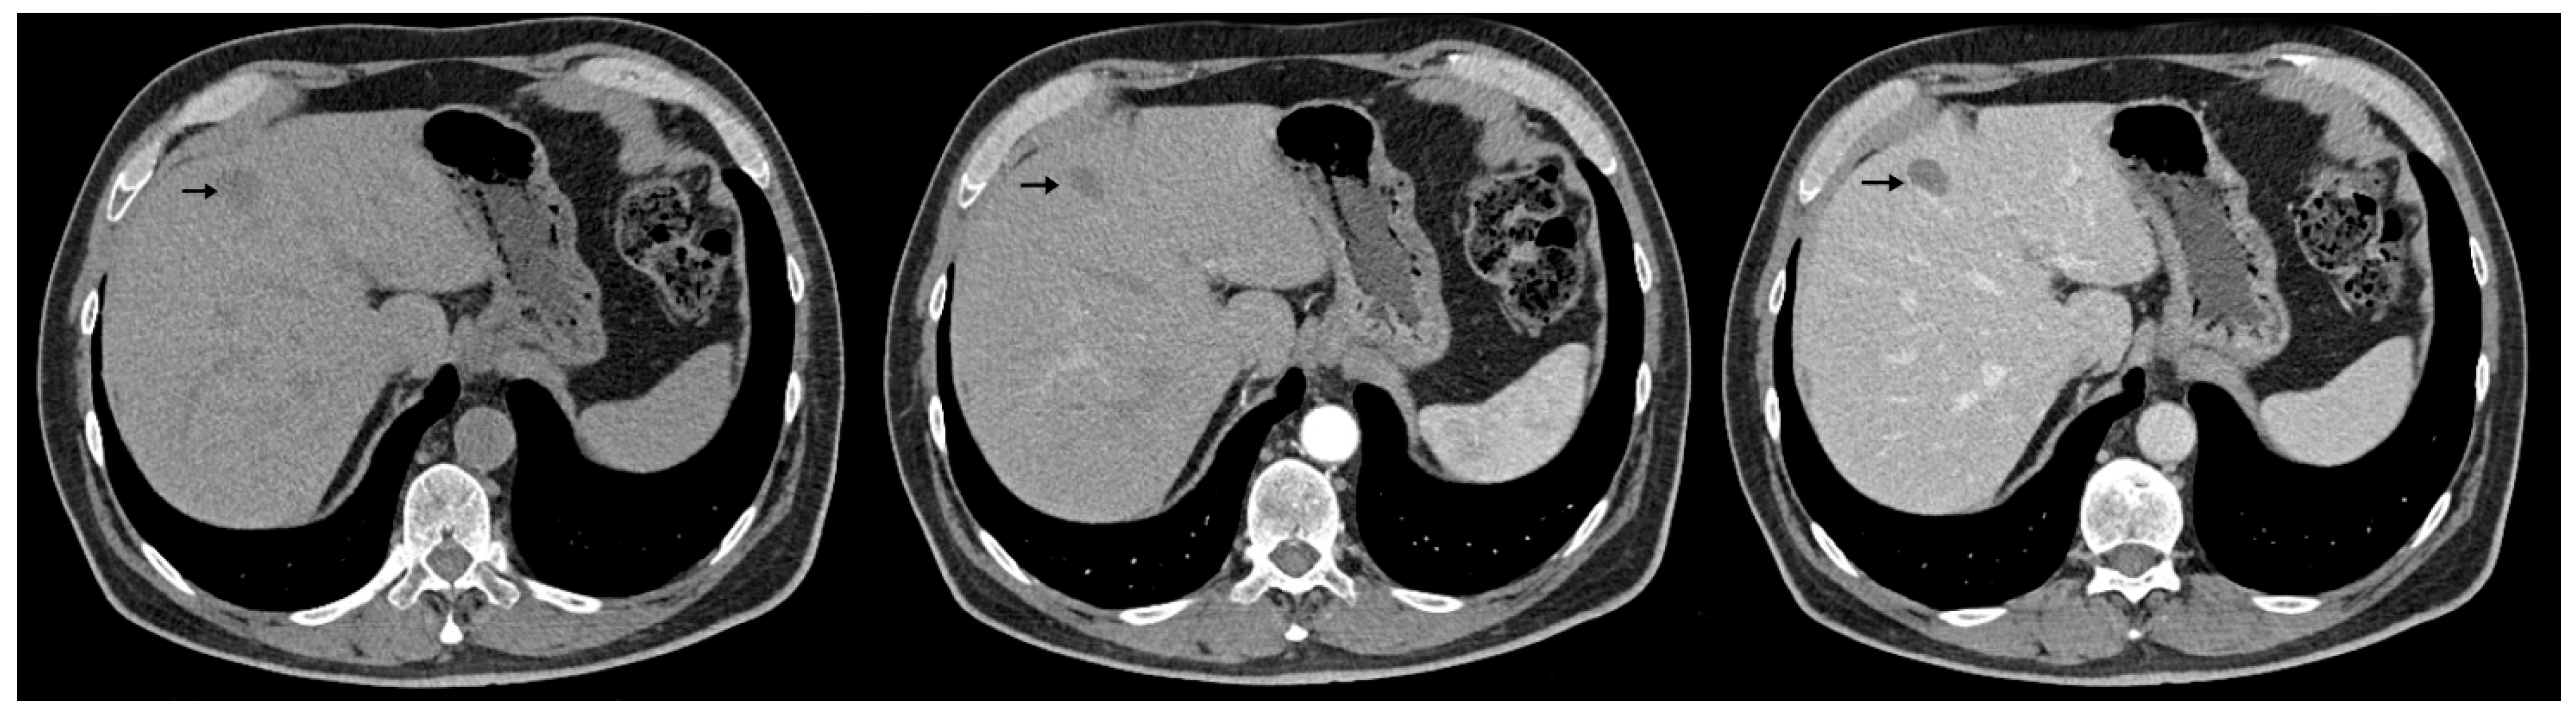

The abdominal contrast-enhanced CT scan further revealed multiple hepatic hypodense nodular lesions, measuring between 1 cm and 3 cm (Figure 6 and Figure 7).

Figure 7.

Contrast-enhanced abdominal CT (axial, non-contrast phase—left, arterial phase—center, and portal venous phase—right) demonstrates two hypodense hepatic nodules (black arrows) with a pseudocapsule appearance—more conspicuous on the portal venous phase—located in segments III and VIII, showing an enhancement pattern similar to Figure 6.